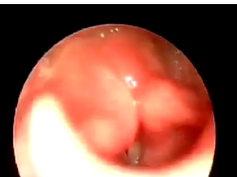

Fiber-optic Laryngoscopic View of a Large Cushion With No Vascular Coloration in a 3-Month-Old Infan

- Date : 01/01/2020

- 0

0

Microlaryngoscopic View of a Cushion With Blue Coloration in a 20-Month-Old Infant

Fiber-optic Laryngoscopic View of a Large Bilobed Cushion With Blue Coloration in a 1-Month-Old Infa

Fiber-optic Laryngoscopic View of a Large Cushion With Blue Coloration in a 1-Month-Old Infant Who I